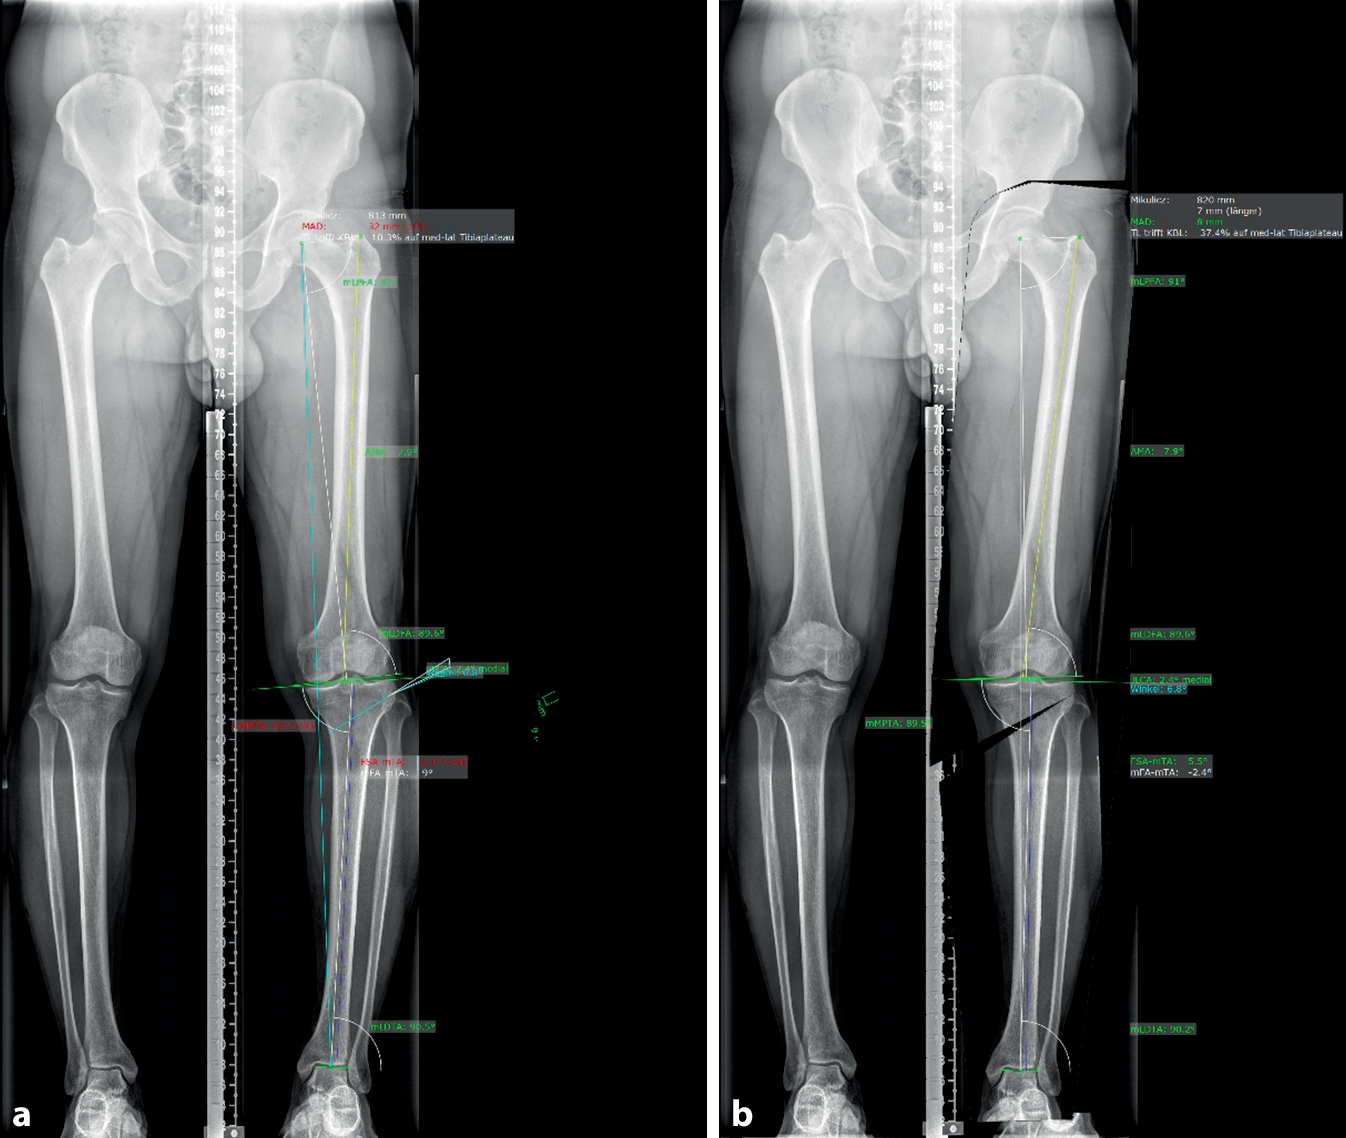

Die klinische Untersuchung zeigte eine regelkonforme „range of motion“ (ROM) im Kniegelenk mit den Werten 5/0/130° und eine Außen‑/Innenrotation von 30/0/15, welche ebenfalls als physiologisch zu betrachten ist. Darüber hinaus konnten weder eine Erschlaffung der Bänder, noch Instabilitäten im Bereich des femorotibialen oder des patellofemoralen Gelenks festgestellt werden. Dennoch konnte ein empfindlicher Punkt am medialen Gelenkanteil ausgemacht werden, welcher sich im Rahmen eines positiven McMurray-Tests auf den medialen Meniskus projizieren ließ. Neben einer anteroposterioren und seitlichen Röntgenaufnahme des Knies, wurden zusätzlich eine präoperative MRT und eine stehende Ganzbeinaufnahmen (Abb. 2) angefertigt. In Letzterer konnte eine varische Abkippung des Tibiaplateaus mit einem mechanischen medialen proximalen Tibiawinkel (mMPTA) von 83 Grad festgestellt werden (Abb. 2a).

Abb. 2

Die beiden Röntgenaufnahmen zeigen die Planung des operativen Eingriffs. a Präoperative Ganzbeinaufnahme des Patienten im anteroposterioren Strahlengang. b Planung der medial öffnenden HTO

Diagnose

Durch die Abweichung des Tibiaplateau-Mittelpunkts nach medial, lässt sich am linken Bein ein Genu varum diagnostizieren. Auch der Winkel zwischen mechanischer Femurachse und mechanischer Tibiaachse (mechanischer tibiofemoraler Winkel, FSA-mTA) mit −1,1 Grad und die mechanische Achsabweichung (MAD) von 32 mm, sind als pathologisch zu werten (Abb. 2a). Zusätzlich lässt sich in der MRT im Bereich der Intermediärzone bzw. des Hinterhorns des medialen Meniskus des linken Beins, ein komplexer radiärer Einriss erkennen. Im Rahmen dessen, konnte auch eine mediale Extrusion des Meniskus festgestellt werden.

Die HTO diente im präsentierten Fall der Korrektur der varischen Beinachse von 9° auf 2,4°. Auch der MAD konnte dadurch von 32 auf 8 mm gesenkt und der FSA-mTA von −1,1° auf 5,5° erhöht werden. Wie oben genannt, zielte dieses Prozedere auf eine adäquate Kraftverteilung und eine Stressabnahme des geschädigten medialen Meniskus ab. Dadurch soll einerseits das Risiko für ein Versagen der Meniskusnaht reduziert und andererseits eine Verbesserung der Symptomatik erreicht werden.